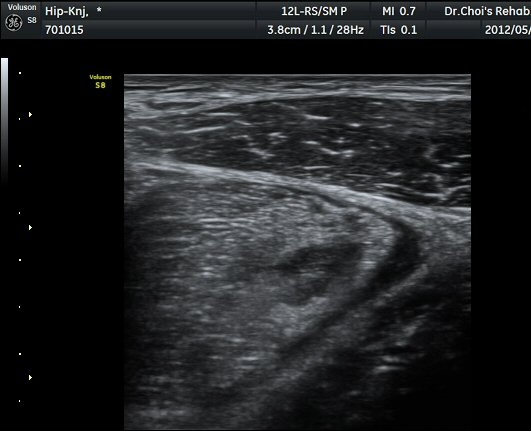

µÚÂÊ ´ëÅð ³»Ãø Ⱦ´Ü¸é°Ë»ç¿¡¼­ À̵ιڱ٠ÀåµÎ ¿ÜÃø¿¡¼­ ±ÙÀ°¼¶À¯¿Í ±Ù¸·¿¡ ÀÇÇØ Çü¼ºµÇ´Â

Á¤»óÀûÀÎ ±ÙÀ°ÀÇ ¸ð¾çÀÌ ¼Ò½ÇµÇ°í Àú¿¡ÄÚ º´º¯À¸·Î °üÂûµÈ´Ù(±×¸² 6). ŽÃËÀÚ¸¦ Á¶±Ý ¸»´ÜÀ¸·Î

À̵¿ÇÏ´Ï Àú¿¡ÄÚ º´º¯³»¿¡¼­ ±¹¼ÒÀûÀÎ ¼ö¾×Àú·ù°¡ °üÂûµÈ´Ù(±×¸² 7, 8).  À̵ιڱ٠ÀåµÎ Á¾´Ü¸é